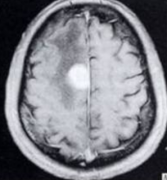

嗅沟脑膜瘤MRI怎么看?手术后会复发吗?MRI(磁共振成像)是诊断嗅沟脑膜瘤的重要影像学工具,其能够提供高对比度、高分辨率的脑部图像,对于肿瘤的位置、...

脑膜瘤 作为一种良性肿瘤,多发生于静脉窦附近蛛网膜细胞,好发部位有额顶叶上矢状窦旁、蝶骨嵴、嗅沟、外侧裂、大脑镰、桥脑小脑角及枕骨大孔区等...

嗅沟脑膜瘤(OGMs)起源于筛板和额筛缝,占全部颅内脑膜瘤的8%-13%。这些肿瘤靠近嗅神经,并倾向于浸润筛状板、周围骨和脉管系统。理想的手术治疗方法是...